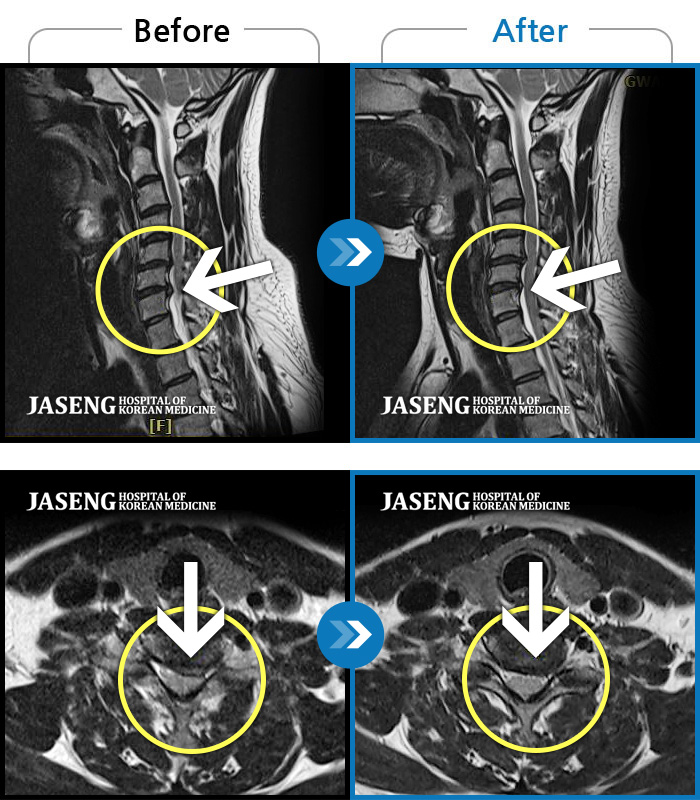

Before

After

환자에게 사전 동의를 받아 동일 조건에서 촬영되었습니다.

개인에 따라 치료 후 부작용이 발생할 수 있으니 의료진과 상담 후 치료를 진행하시기 바랍니다.

교통사고로 인해 기존의 퇴행성 디스크가 파열되어 극심한 경추의 통증과 손의 힘 빠짐, 손가락의 저림 증상을 호소하였음